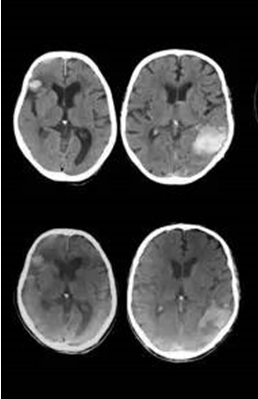

(1)胶质瘤手术:胶质瘤的理想手术方案是全切肿瘤并保留正常脑功能,但实际手术中很难做到这一点。尤其是肿瘤位于重要功能区(中央区及顶叶、丘脑、岛叶等)时,当神经外科医生视觉判断脑胶质瘤已全切时,仍有病例有肿瘤残余。即使应用常规神经导航,也有近1/3病例发生肿瘤残留。切除程度是胶质瘤最主要的预后相关因素之一。术中最大限度减少瘤负荷,不仅有利于后续规范化综合治疗,而且能延长肿瘤无进展期与生存时间。对于脑胶质瘤,iMRI可以实时、精确、定量地监控手术切除范围,是当前脑胶质瘤显微手术的最高科技,其远期临床疗效已得到国际医学界肯定。(2)垂体大腺瘤:采用iMRI引导神经内镜下经鼻-蝶切除术。高场强iMRI能够即时反馈肿瘤切除范围,并显示邻近海绵窦、颈内动脉、视交叉及下丘脑等重要结构,对侵袭到海绵窦内的肿瘤可以在术中及时发现,提高手术全切率和精确性以及安全性。

(3)脑血管病手术,如海绵状血管瘤、脑动静脉畸形等,有部分位于深部,且肿瘤微小,应用iMRI,结合术中实时导航,可有效解决病变漂移,精确定位病变。